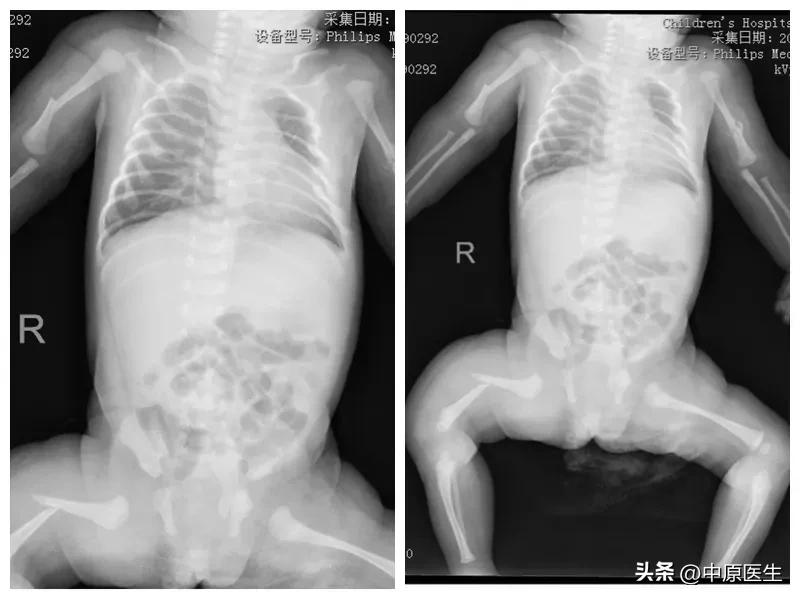

随后,悦悦被送去拍了X光片,结果显示,悦悦体内竟然有陈旧性的骨痂!

陈旧性的骨痂,说明悦悦的骨折不是刚刚发生,断骨周围已经形成痂,由此判断,孩子在妈妈肚子里时就已经骨折!

科室主任许邦礼、主治医生林法涛为孩子做了查体后,紧急与医学影像科联系进行床旁拍片,结果显示肋骨、锁骨、肱骨、股骨、坐耻骨多处骨折!